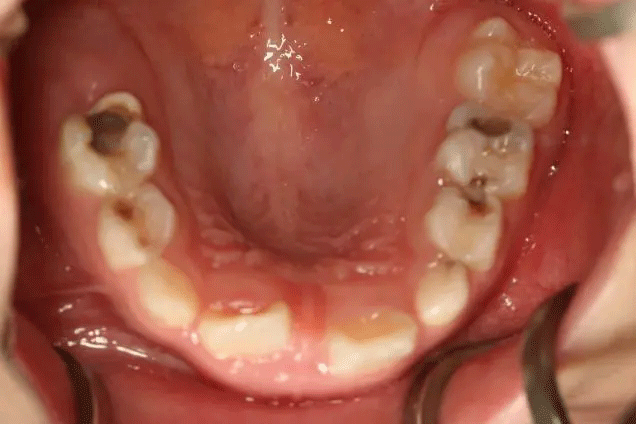

孩子1歲開始已經(jīng)出現(xiàn)齲齒

但是媽媽2年后才帶孩子就診

這時,孩子已經(jīng)斷斷續(xù)續(xù)疼了3年

在門診中發(fā)現(xiàn)

來口腔科檢查的孩子

有些牙齒都已經(jīng)爛得很嚴重了

甚至牙齒幾乎都爛光僅剩下牙根

孩子不喊疼,家長很少會帶來看牙